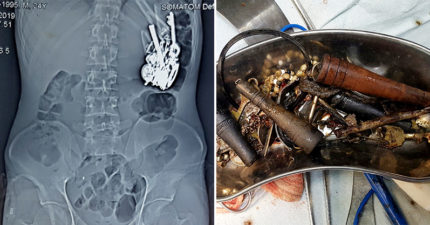

他肚子痛照X光體內竟找到「80個雜物」 醫生:鑰匙都生鏽了…

June 22, 2019

世界